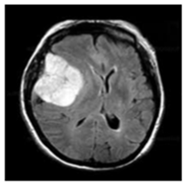

| No Tumor | Glioma Tumor | Meningioma Tumor | Pituitary Tumor | |

| Brain MRI Images |  ![]()  |  ![]()  |  ![]()  |  ![]()  |